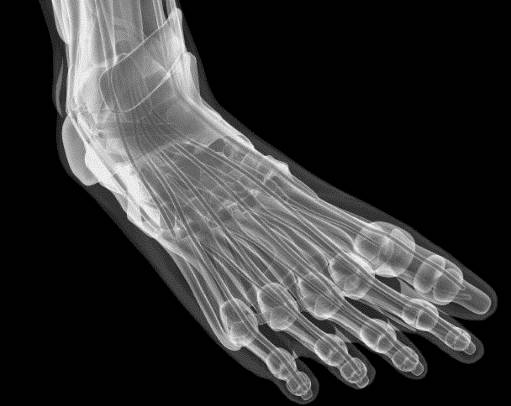

Что такое синовит голеностопного сустава, как он выражается? Это воспалительный процесс, происходящий во внутренней оболочке суставной сумки и характеризующийся скоплением жидкости в полости сустава. Синовиальная оболочка выстилает всю внутреннюю часть суставной сумки и выполняет важные функции. В первую очередь она обеспечивает защиту суставных структур от внешних повреждений, выполняет амортизационную функцию и улучшает подвижность сустава.

При воспалении, или синовите, происходит избыточное выделение внутрисуставной жидкости. Это нарушает нормальное питание суставных структур и приводит к дегенеративно-дистрофическим процессам в них. Данная патология, как правило, в одноименных суставах наблюдается только с одной стороны. Лечение болезни зависит от причины ее возникновения. Помощь оказывают различные специалисты — ортопед, ревматолог, гематолог.

При остром синовите обычно развивается яркая клиническая картина. В первую очередь пациента беспокоит интенсивная боль в области голеностопа, которая усиливается при незначительной физической нагрузке и пальпации. Подвижность сочленения значительно снижается. В области голеностопа постепенно формируется выраженный отек периартикулярных тканей. Постепенно появляются признаки нестабильности сустава.